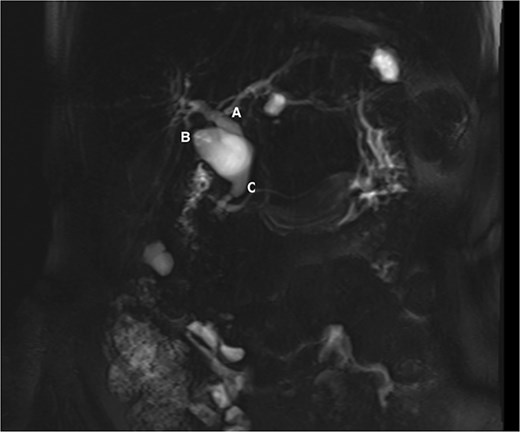

Following her pancreatitis episode, MRCP was performed to identify a possible etiology. Imaging revealed cyst dilatation of the cystic duct and concomitant CBD dilatation (Fig. 1). Physical examination showed no jaundice or palpable masses. Laboratory tests were within normal limits.

MRCP showing the common hepatic duct (A), cystic duct dilatation of 23 mm (B), and common bile duct of 14 mm (C).